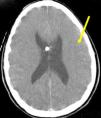

Our patient is a 35-year-old woman admitted to the neurosurgery department for scheduled surgical treatment of chronic hydrocephalus secondary to idiopathic stenosis of the aqueduct of Sylvius. In the preceding 10 months, she had experienced increased frontal headache and fluctuating memory changes. Findings from the neurological exam were limited to slightly diminished visual acuity. Magnetic resonance imaging (MRI) showed triventricular hydrocephalus (Fig. 1A–C). Presurgical cardiological evaluation revealed no cardiac changes (Fig. 2A and B). Presurgical blood pressure was 126/84mmHg. With the patient's informed consent, we proceeded to perform an endoscopic third ventriculostomy and found no elevated intracranial pressure. The external ventricular drain was placed on the right lateral ventricle. Nine hours after the surgery, while the patient's status was good, she began to develop symptoms of sudden-onset headache and progressive decrease in level of consciousness, with subsequent decerebrate rigidity, right-sided mydriasis, intracranial hypertension, altered heart rate, and arterial hypotension. The patient was intubated and transferred in coma to the intensive care unit. A transthoracic echocardiogram showed dilated left ventricle with akinesia of the lower interventricular septum, lateral and posterior hypokinesia, and an ejection fraction of 38%. Electrocardiogram revealed widened QRS complex, inverted T wave, and ST segment elevation (Fig. 2C and D). Levels of cardiac enzymes were high. Initial brain computed tomography revealed diffuse subarachnoid haemorrhage (Fig. 3). Three days after onset of coma, we performed an electroencephalogram that showed no brain activity. Our patient died 5 days later due to acute heart failure. We were unable to perform an autopsy because the patient's family did not give consent.

Presurgical imaging studies (A and B): T1-weighted brain MRI without contrast that revealed triventricular hydrocephalus. Evans index was 0.43 (B) and third ventricle diameter was >1.4cm (A). Presurgical study (C): T2-weighted MRI showing increased convexity of the corpus callosum, flattening of the midbrain, and stenosis of the aqueduct of Sylvius. Postsurgical studies (D): T1-weighted MRI without contrast that revealed decreased ventricular size, upward displacement of midbrain, and the endoscope path for the third ventriculostomy.